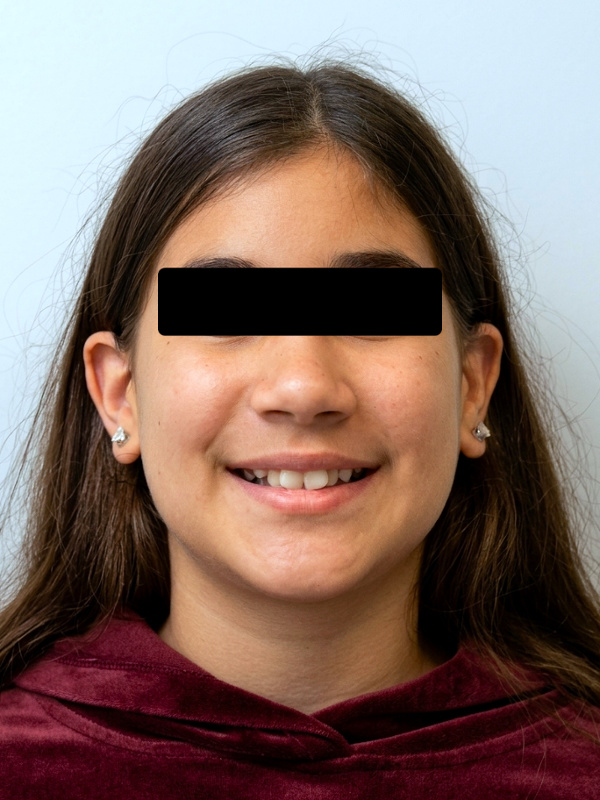

As a specialized orthodontist, utilizing traditional braces and Rapid Palatal Expansion (RPE) for preteens allows us to efficiently correct severe skeletal and dental crowding. Over the course of this 30-month treatment, we addressed a notably narrow maxilla. By expanding the palate during this crucial growth phase, we established the necessary arch width to properly accommodate and align the erupting permanent teeth into a functional, healthy smile. At our concierge Miami and Kendall offices, we prioritize meticulous clinical outcomes for every age group. We invite you to schedule a personal evaluation to discuss your child's orthodontic needs, ensuring the specialist evaluates every case personally from the initial consultation to the final result.